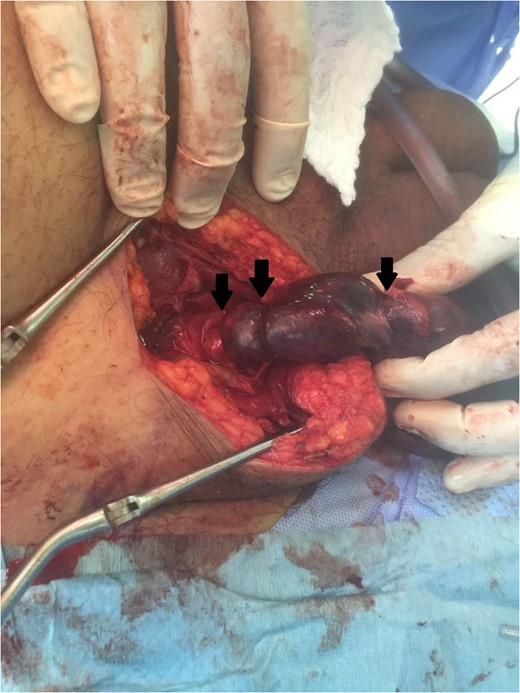

A 63-year-old gentleman who is a known case of dyslipidemia was presented to our Emergency Department with a right sided scrotal swelling and pain for 1 week. The patient had been having right testicular pain for the past 6 months on and off but never sought medical advice. On clinical examination, the patient had right scrotal swelling with epidydimal and cord tenderness and swelling, the cremasteric reflex could not have been assessed due to the large size of the scrotum with reactive scrotal wall edema. The patient underwent Doppler ultrasound which showed right testicular heterogeneous echotexture with nodular hypo-echoic areas (Fig. 1) with preserved vascularity. There was no evidence of testicular torsion or masses in that study. A provisional clinical correlation was made and the patient was diagnosed with right epididymo-orchitis and discharged home on oral antibiotics. Next day, the patient presented again to our ER with increased pain, swelling and erythema reaching the right inguinal area. So, the patient was admitted for administration of intravenous antibiotics. After 2 days of IV antibiotics, the patient’s condition was not improving which prompted the need of a CT scan. CT scan showed a heterogeneous enlarged right testis with twisting of the spermatic cord at the level of inguinal area and scrotal neck (Fig. 2). A diagnosis of testicular torsion was made based on these findings. The patient then underwent an urgent exploration with an inguinal incision which showed a hugely edematous cord, the incision was extended as Hockey-Stick incision and the right testis was delivered. The testis was dark, edematous, with no evidence of palpable testicular masses. The spermatic cord was twisted in 1080° clockwise fashion in three areas (Fig. 3). The first 360°, torsion was at the level of the deep inguinal ring, the second at inguinal part of the spermatic cord, and the third is just proximal to the testis. Right radical orchiectomy was carried out with high ligation of the spermatic cord at the level of deep inguinal ring, which was the site of normal, non-engorged cord. The procedure was completed with the extended inguinal incision with no violation of the scrotum, since the pathology was high in the inguinal area. The patient recovered very well with no complications.

An intra-operative photo showing torsion areas (black arrows).